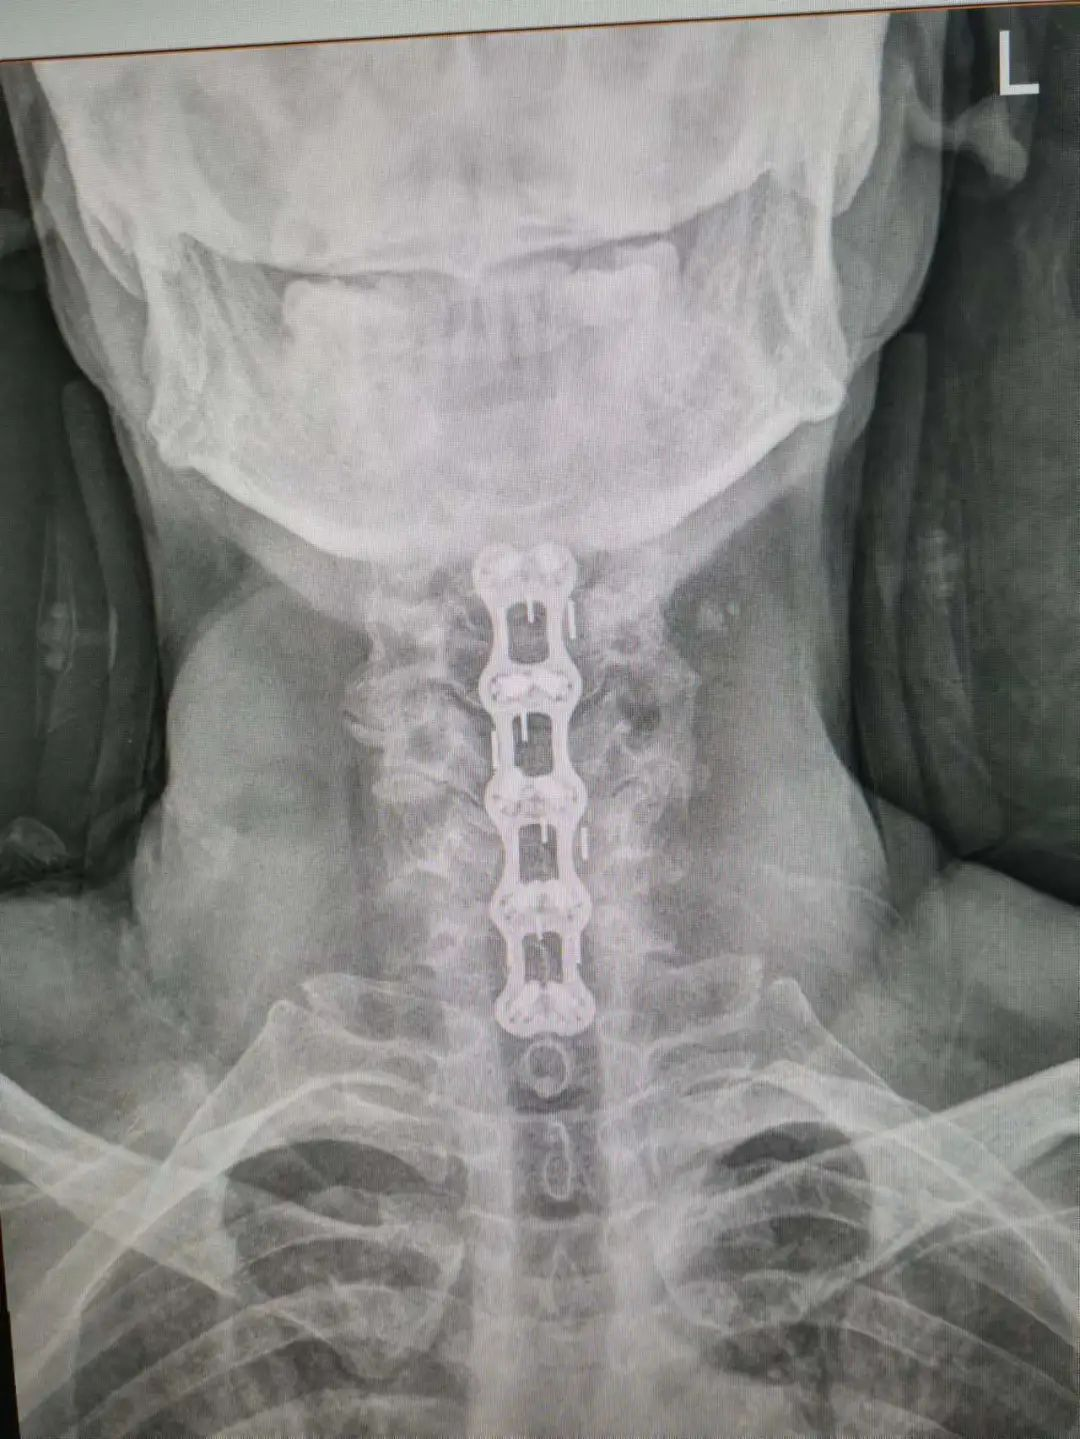

楊先生脊髓性頸椎病拍片

由于楊先生的病情嚴重,需住院治療。楊先生入院后,瀘州市中醫(yī)醫(yī)院骨傷二科科主任楊陳一制定了手術計劃,決定脊髓型頸椎病的手術從前路切開減壓,頸3/4 、頸4/5、 頸5/6、 頸6/7椎間盤切除,椎間融合,鋼板內固定術手術,而腰椎管狹窄癥經后路切開減壓,腰3/4、腰4/5椎同盤動除,椎間融合、釘棒系統(tǒng)內固定術。

楊先生術后拍片